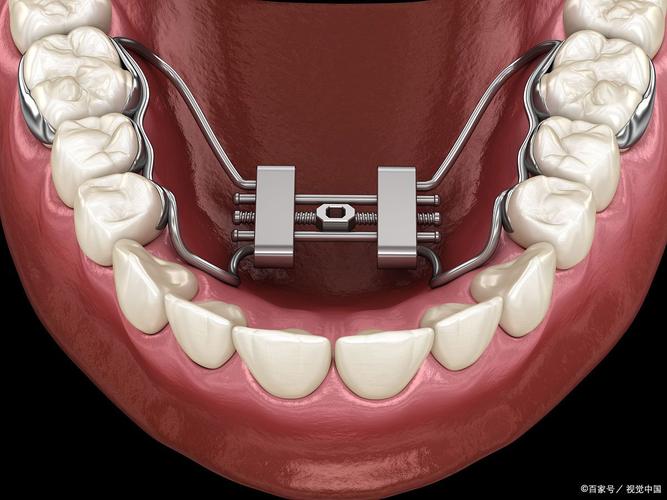

Damon系统的核心突破在于“自锁托槽”结构和“生物力学轻力”理念,传统托槽依赖结扎丝或橡皮圈固定弓丝,弓丝与托槽间摩擦力较大,牙齿移动需较大力量且速度较慢;而Damon托槽通过内置的滑盖或锁片结构,将弓丝直接“锁”在托槽槽沟内,无需结扎,弓丝可在槽沟内自由滑动,这种设计大幅降低了牙齿移动时的摩擦力(摩擦力仅为传统托槽的1/5-1/3),使牙齿在持续、轻柔的生物力作用下实现高效移动,同时减少对牙周组织的刺激。

- 粘接托槽:清洁牙齿酸蚀后,将Damon托槽精准粘接在牙面,安装初始镍钛弓丝,开始轻力移动牙齿。